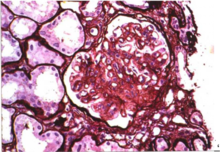

中度系膜增生重度:系膜瀰漫增生基礎上呈團塊聚集,毛細血管結構破壞,

系膜細胞>5個

重度系膜增生病理病因